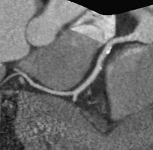

Рис. 2. - Изображение коронарных артерий (MPR

реформация) при

частоте пульса 95 ударов в минуту без

использования премедикации.

Отсутствие динамических артефактов